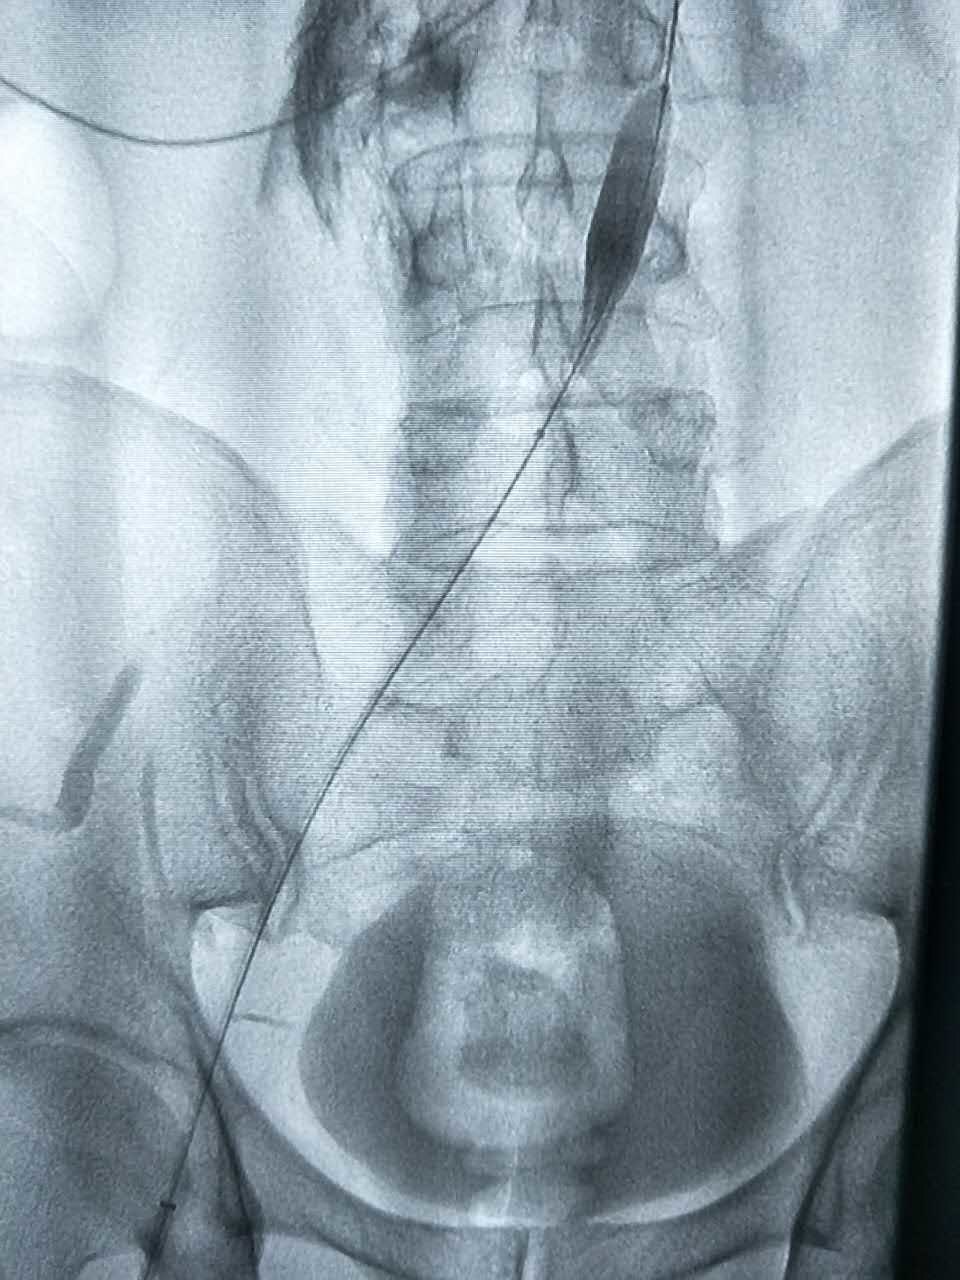

腿肿的原因分析

960x1280 - 142KB - JPEG